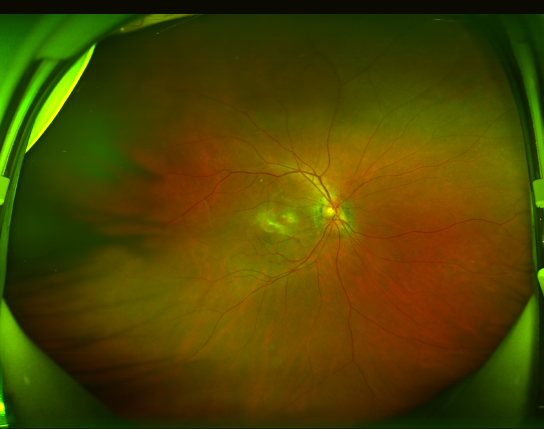

患者张阿姨(化名)自今年2月起发现右眼视物变形、中央视野出现暗影,经昆明艾维眼科医院眼底病科何雨檀主任接诊检查,确诊为渗出型老年性黄斑变性。通过光学相干断层扫描(OCT)显示黄斑区存在明显新生血管及出血病灶,荧光素眼底血管造影(FFA)进一步明确病变范围。何主任团队为其制定个性化抗VEGF药物治疗方案,配合光动力疗法(PDT),经过3次玻璃体腔注药治疗后,患者视网膜下积液吸收,最佳矫正视力显著改善。

患者治疗前的眼底照相和OCT检查